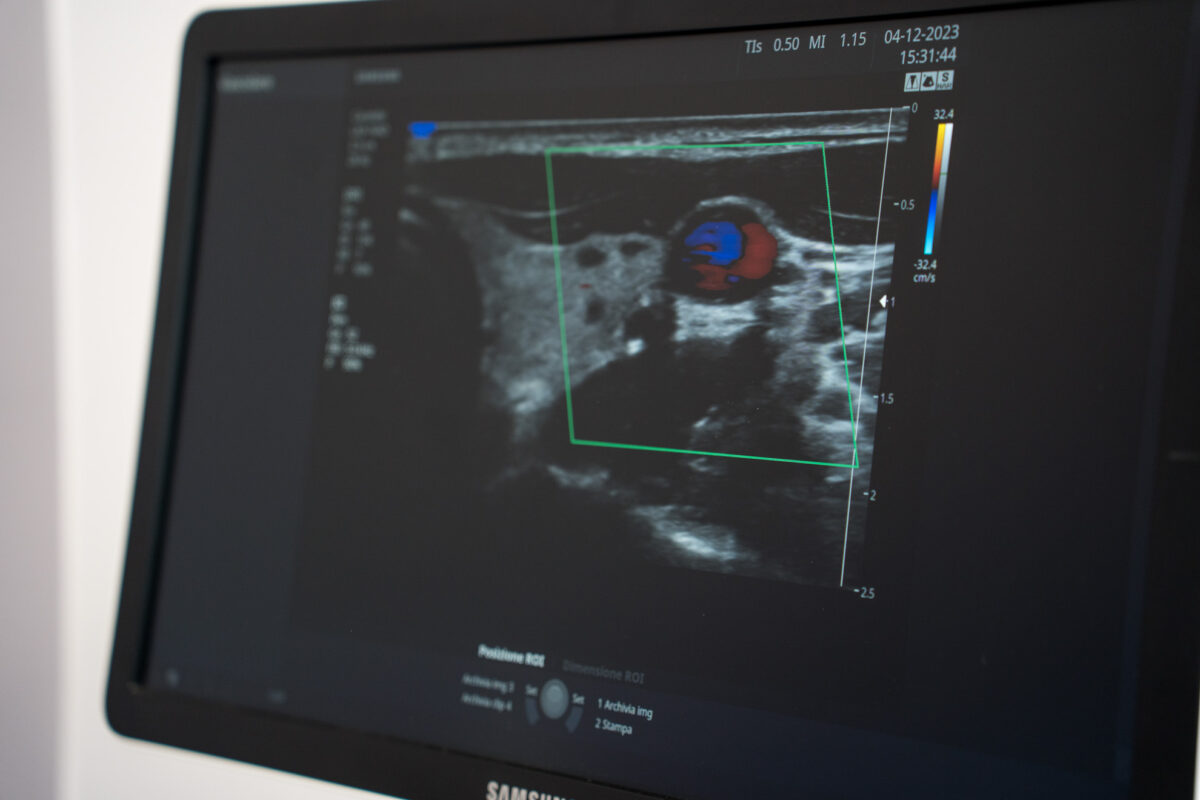

ECO-COLOR-DOPPLER DEI VASI INTRACRANICI PER LO STUDIO DELLO SHUNT DESTRO-SINISTRO

La metodica, richiedendo l'impiego di mezzo di contrasto (microbolle d'aria) prevede la presa visione, esatta comprensione e firma del consenso informato al paziente circa la procedura in atto.

L'esame viene condotto posizionando il Paziente supino con l'operatore seduto dietro alla testiera del lettino; si esegue un'eco-color-doppler dei tronchi sovra-aortici per valutare la presenza di alterazioni vasali.

Successivamente l'operatore cerca con la sonda ecografica di identificare il segnale dell'arteria cerebrale media attraversando con gli ultrasuoni le suture tra le ossa che costituiscono il cranio, impiegandole come finestre acustiche (temporale o occipitale).

In soggetti di età avanzata può verificarsi una calcificazione completa delle suture ossee con conseguente impossibilità ad insonare il vaso bersaglio e di conseguenza impossibilità a completare la procedura. Una volta identificata la finestra migliore e l'arteria cerebrale media, un infermiere reperisce un accesso venoso in una vena antecubitale (nel braccio).

Si registra il flusso arterioso spontaneo nell'arteria cerebrale media, dopo infusione endovenosa del mezzo di contrasto e durante una manovra di Valsalva (espirazione forzata a glottide chiusa). A seconda di alcuni parametri si può capire se esiste un forame interatriale nel cuore.

L'utilità dell'esame è quella di riuscire ad idenficare la presenza di “buchi” anche veramente piccoli nel setto cardiaco che separa l'atrio destro da quello sinistro.

Se l'esame è NEGATIVO ( non ci sono buchi) certamente non ci sono difetti, se l'esame è POSITIVO è necessario proseguire le indagini con una ecocardiografia transesofagea (indagine modestamente invasiva, ma necessaria per evidenziare posizione e dimensioni del difetto interatriale, vista la vicinanza tra l'esofago e la parte del cuore che si deve studiare).